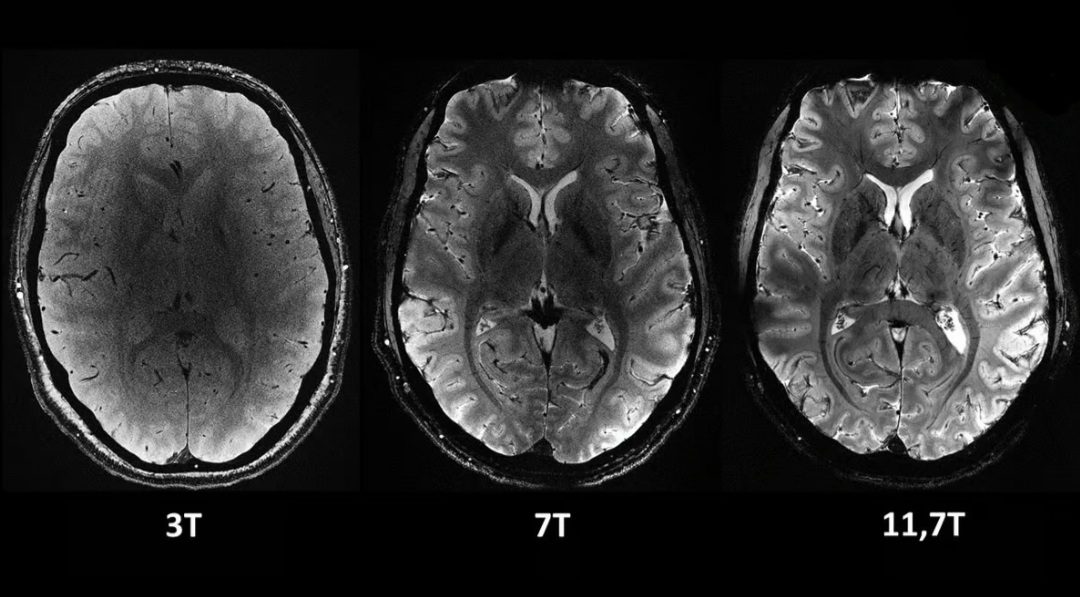

دستگاه Iseult MRI که توسط کمیسیون انرژیهای جایگزین و انرژی اتمی فرانسه (CEA) توسعه یافته است، دارای قدرت میدان مغناطیسی 11.7 تسلا (T) است. در مقایسه، دستگاههای MRI معمولی که امروزه در بیمارستانها به طور گسترده مورد استفاده قرار میگیرند، معمولاً 1.5 یا حداکثر 3 T هستند.

مزیت اصلی این قدرت اضافی این است که میتوان تصاویری با وضوح بسیار بالاتر از مغز را بسیار سریعتر گرفت. تنها در چهار دقیقه، Iseult میتواند تصاویری تا 0.2 میلیمتر از بافت مغز را به صورت افقی، در برشهایی به ضخامت 1 میلیمتر ثبت کند. این حجم معادل چند هزار نورون در یک زمان است.

تصاویر مقایسه ای از مغز انسان که با دستگاه جدید Iseult MRI در سطوح مختلف قدرت گرفته شده است. همه این تصاویر در مدت زمان یکسانی گرفته شدهاند و نشان میدهد که چقدر میتوان جزئیات بیشتری را با آن گرفت.